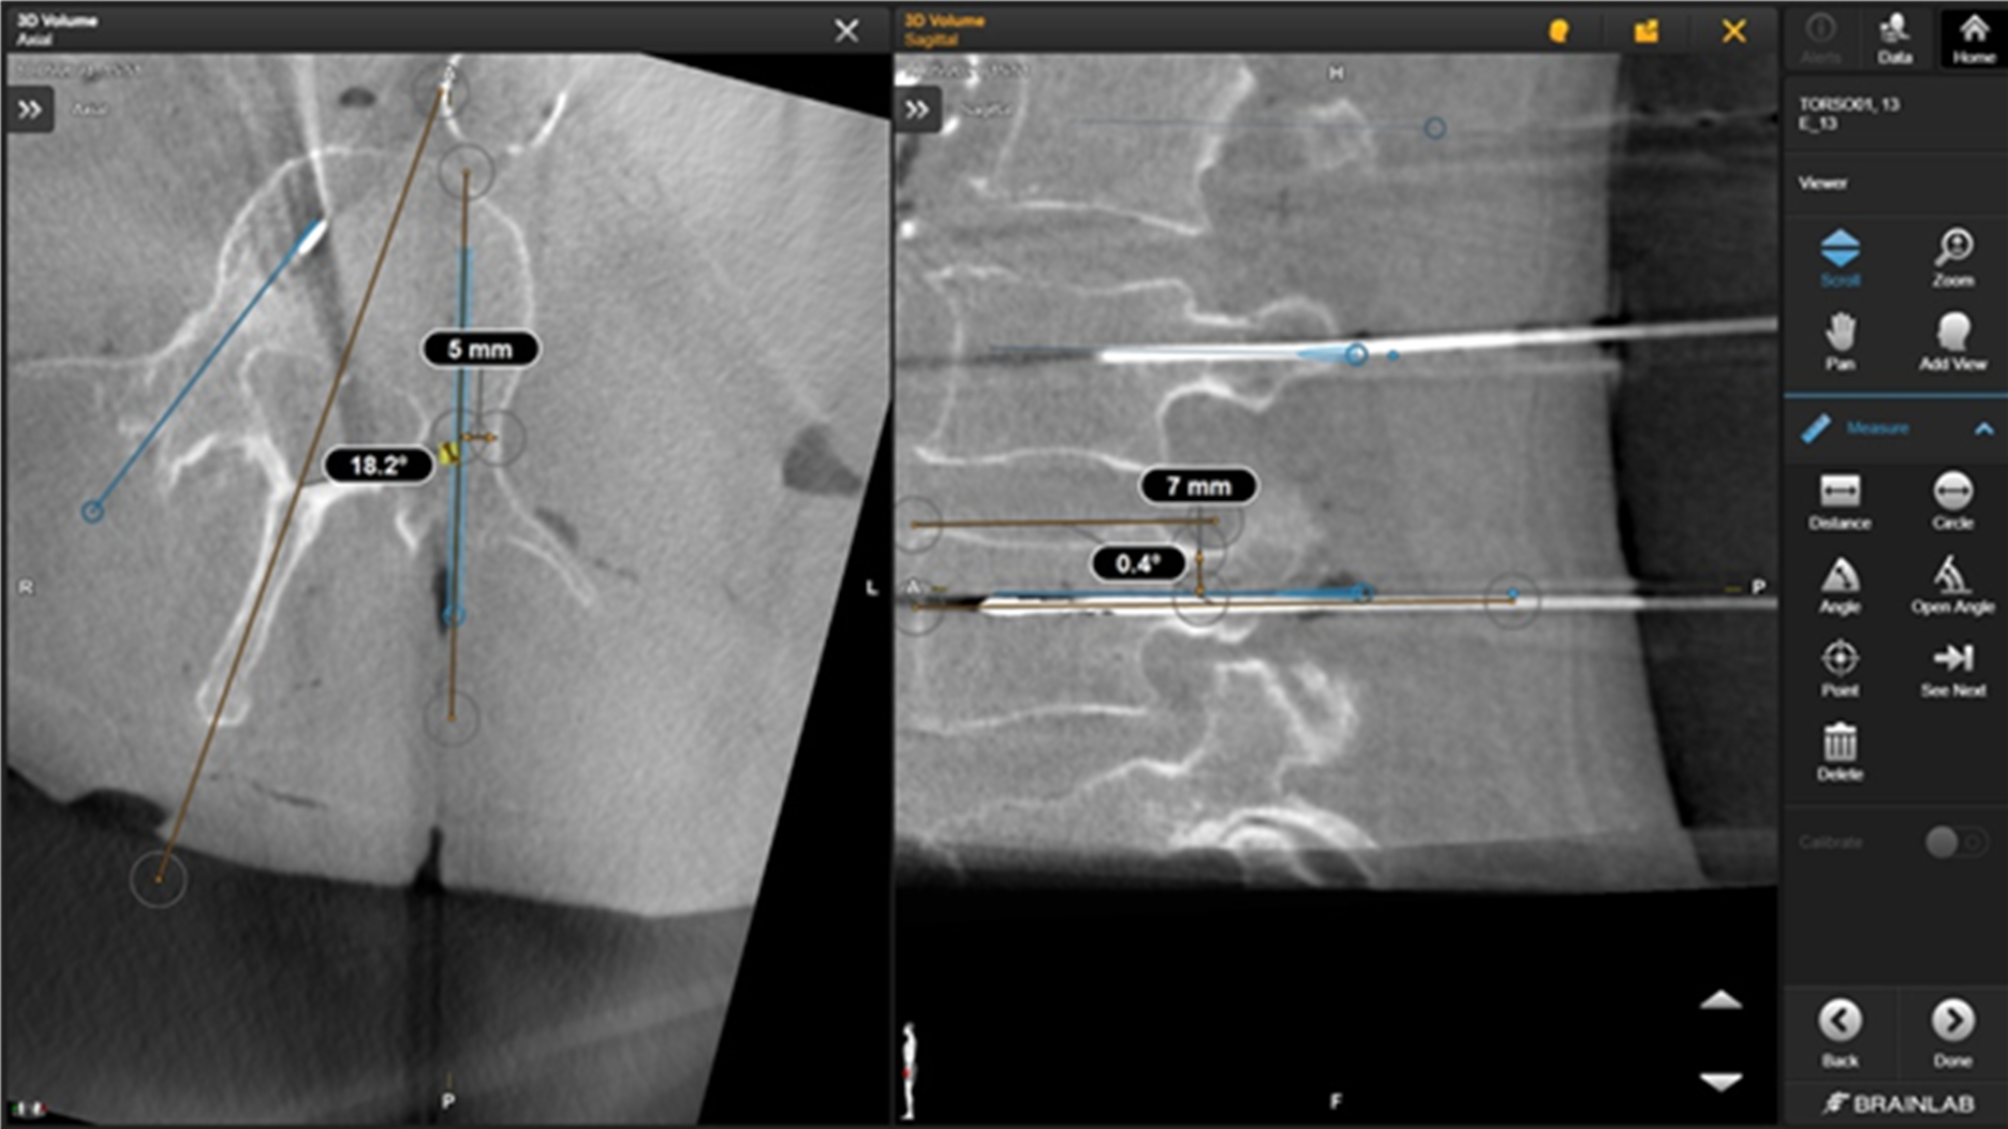

Fig. 7

Measurements after image fusion.